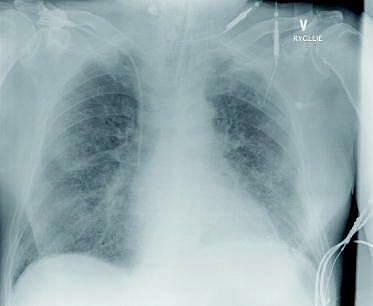

En 74-årig mand var blevet behandlet med penicillin af sin egen læge og senere med roxithromycin pga. uproduktiv hoste og åndenød. Han blev indlagt med forværring af luftvejssymptomerne. På trods af intravenøs behandling med penicillin og erythromycin progredierede symptomerne, og efter seks dage opstod der behov for respiratorbehandling. Efter en kortvarig stabilisering forværredes tilstanden, og patienten fik kredsløbsshock og nyresvigt (akut tubulær interstitiel nefropati, ATIN). Efter ti dage blev han overflyttet til et andet hospital mhp. dialyse. Der skiftedes til bredspektrede antibiotika: meropenem og ciprofloxacin. Alle mikrobiologiske undersøgelser for bakterier i forløbet viste negative resultater. En røntgenundersøgelse af thorax viste bilaterale udbredte interstitielle infiltrater.

En hurtigtest for influenzavirus i trakealsekretet gav positive resultater og blev efterfølgende konfirmeret som type A med polymerasekædereaktion-teknik. Patienten døde af kredsløbssvigt 25 dage efter symptomdebuten.

Konklusion: Influenzavirus kan forårsage en svær pneumoni med interstitielle infiltrater, som kan konstateres på et røntgenbillede af thorax og ved symptomer på akut respiratorisk distress- syndrom (ARDS). Influenza kan forebygges med vaccination. Sygdomsforløbet kan afkortes ved hurtig indsat behandling med osetalmivir.